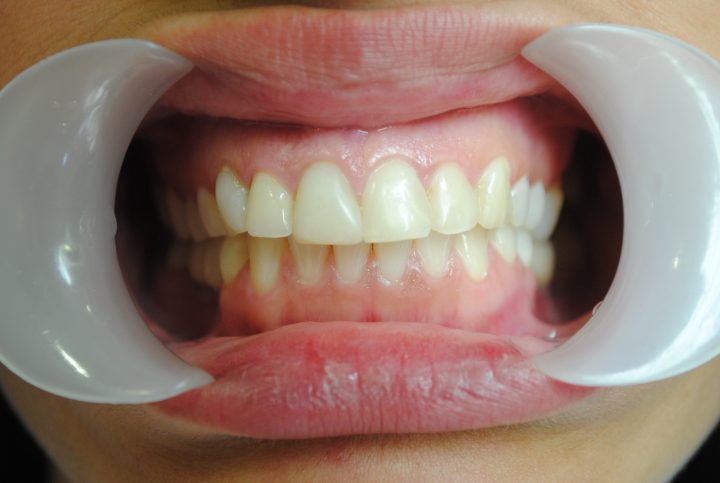

Sofie

Sofie ist eine 43-jährige norwegische Patientin. Seit mehreren Jahren hat sie nur gesehen, dass ihre Zähne abnützen und verkürzen. Sie wurde mit diesen Zähnen immer älterer ausgesehen. Seit ihrer Kindheit hat die durcheinanderstehenden Zähnen sie gestört, und unten linkt hat sie eine Zahnlücke, die beim Essen sehr unangenehm war. Aus diesen Gründen hat sie uns aufgesucht,

Sofie musste nur einmal nach Budapest zu fahren, und wir konnten ihr Lächeln vervollkommnen: Im Ablauf 10 Tagen wurden auf der oberen Region 14 metallfreie Krone, auf der unteren Region 10 Zirkonkronen und eine, aus 4 Stück stehende Brücke bearbeitet.

Sie hat angezeigt, dass sie sich vor 20 Jahren nicht wohlgefühlt hat, aber jetzt schon- Diese Entscheidung war das Beste, dass sie diese Behandlung in der Zahnklinik Centrocc Dental machen gelassen hat.